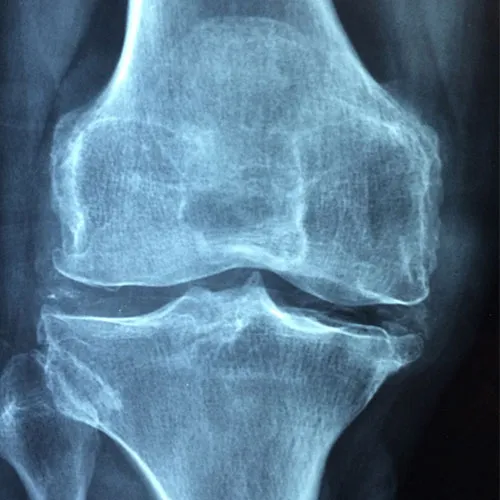

Osteoporosis